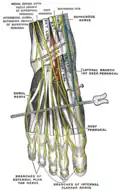

Nerfs profonds à l'avant de la jambe. Nerfs du dos du pied.

Nerfs du dos du pied.